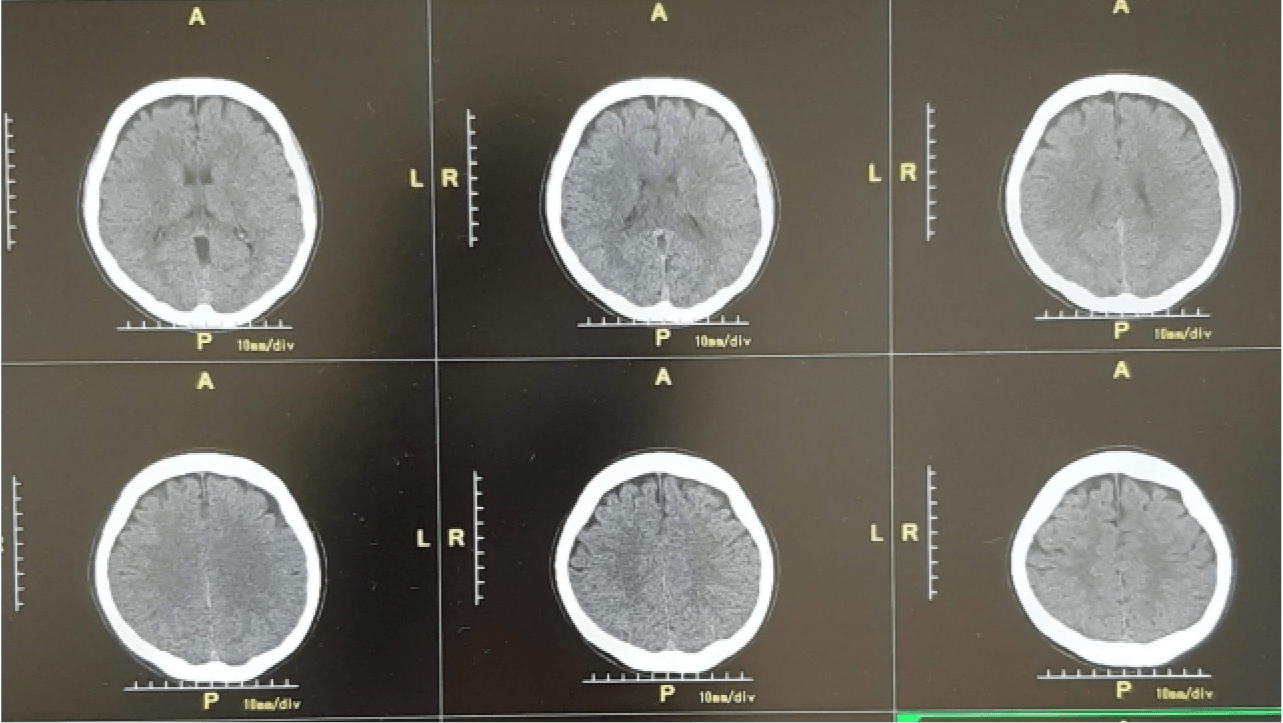

画像取付け

医療機関で撮影された画像も、後遺障害診断書同様に調査を行う上で重要な資料となります。

申請前に既に画像を取り付けている場合は申請時に一緒に送りますが、取り付け前でしたら、調査事務所より画像の取り付け依頼書類が届きます。